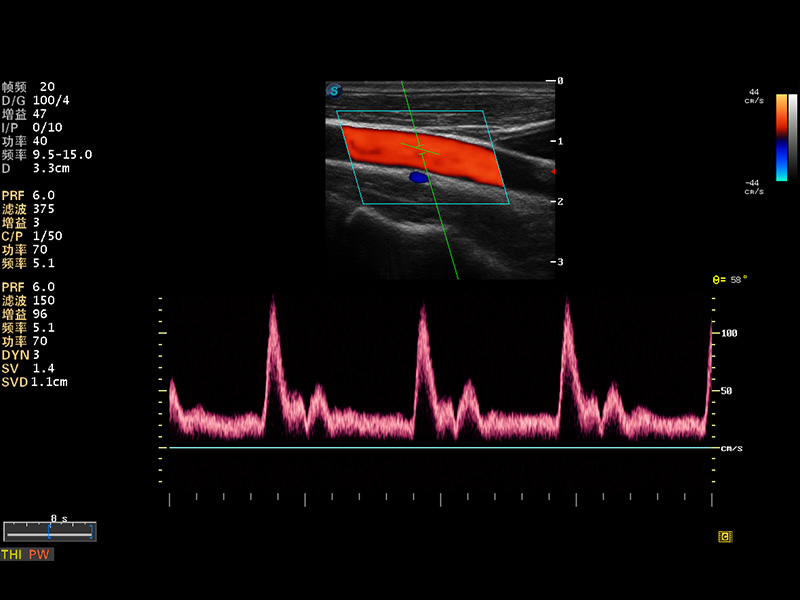

S8 EXP便携式彩色多普勒超声诊断仪是1xBET研发的高端全身应用型便携彩超。高通道的VIS平台融合可视化(Visual)、智能化(Intelligent)和人性化(Smart)的特点,配以1xBET自主研发生产的探头大家族,使您能够快速、准确的获得病人信息,提高工作效率的同时减轻疲劳。

成像技术

多波束形成器

μ-Scan微米成像

谐波成像

实时宽景成像

空间复合成像

3D/4D成像